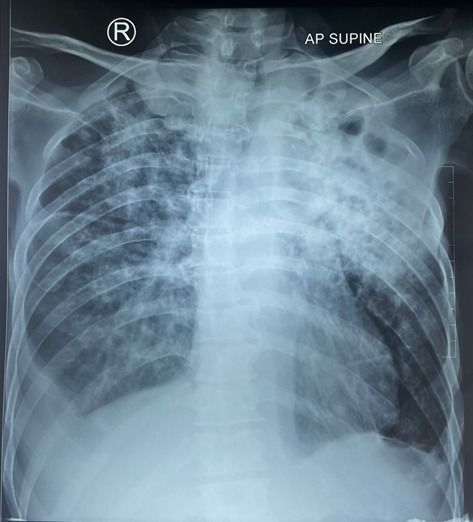

Map: Yellow Skin and Worsened Cough (1129)